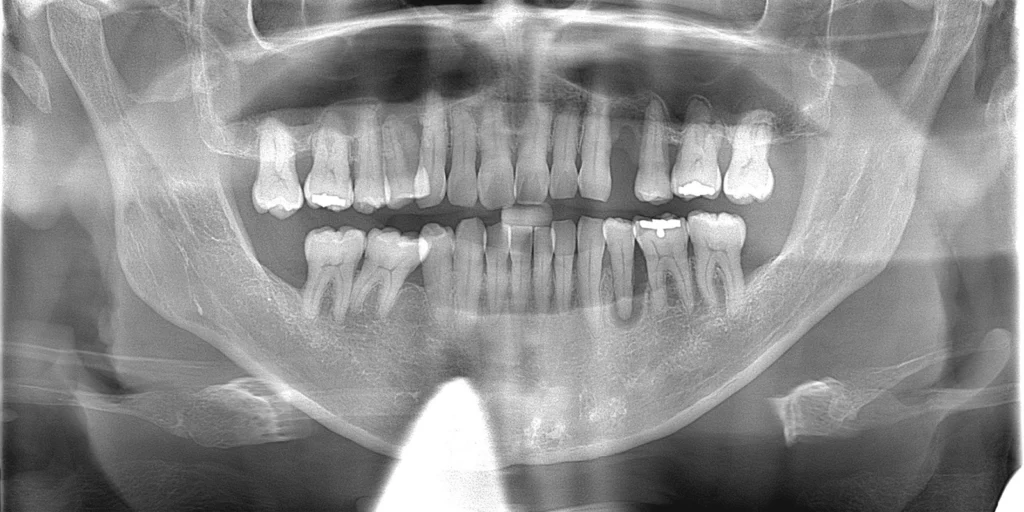

歯が割れたり親知らずなど、やむをえず歯を抜いた後、心配なのは出血や抜歯後の痛みだと思います。

当院では、抜歯後にテルプラグという抜歯創用保護材を填入することをお勧めしています。

テルプラグを抜歯窩に填入することにより、傷口の保護、肉芽形成を促し、痛みを和らげる効果が期待されます。